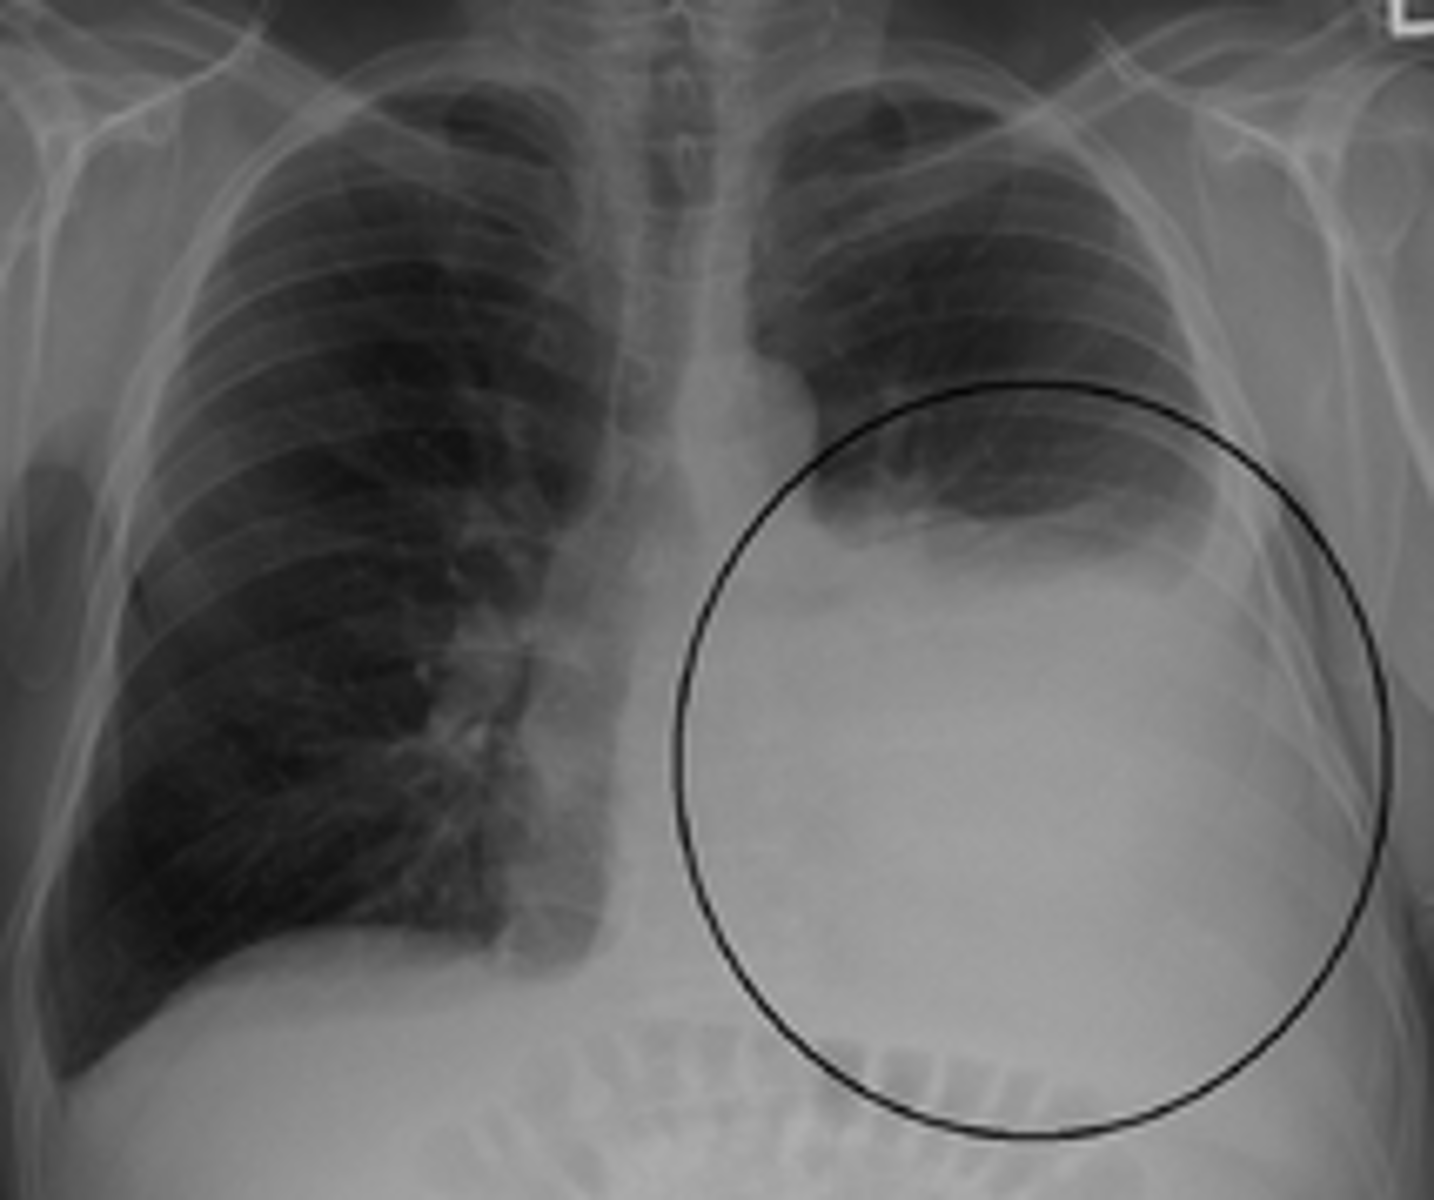

chylothorax

presence of chyle in the pleura, caused by disruption or dysfunction in the flow of chyle through the thoracic duct

dyspnea without chest pain, as chyle does not invoke an inflammatory response

presentation of chylothorax

-thoracentesis with pleural fluid analysis

-milky appearance, predominantly lymphocytes

-high protein, no glucose, pH 7.4-7.8

-high TGs

diagnostic findings of chylothorax